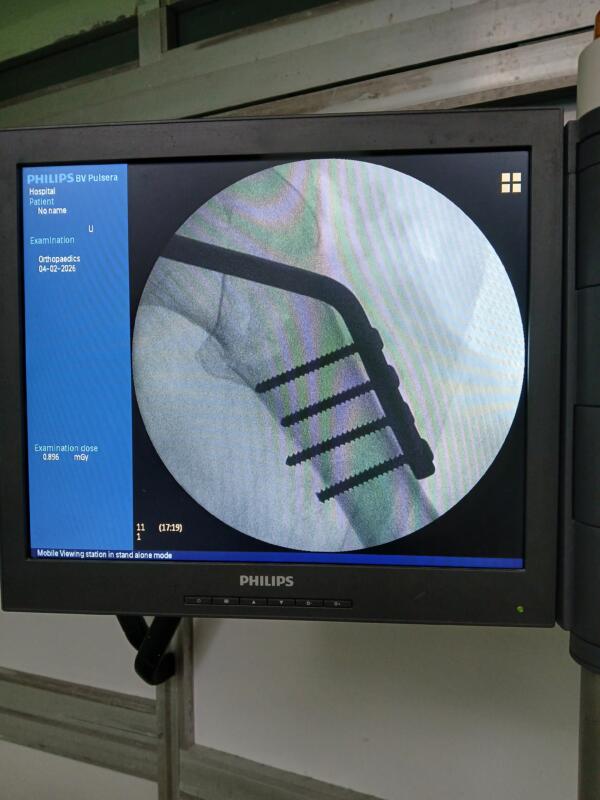

Una cirugía de cadera puede demandar hasta 7 tornillos corticales de 4.5 milímetros. Foto cortesía del entrevistado.

Para esa fijación se usan tornillos, placas, clavos, sistemas de compresión y otros dispositivos de osteosíntesis. Entre ellos están los tornillos corticales de 4.5 milímetros, pensados para hueso cortical denso y para grandes fragmentos, con medidas y usos ampliamente estandarizados en los sistemas de trauma. También existen los tornillos esponjosos, diseñados para el hueso menos denso: presentan una rosca más gruesa y separada, lo que favorece el anclaje en la esponjosa ósea.

El equipo pensó en un tornillo esponjoso, que ya existía como producto comprado en el exterior y aprobado para uso médico y se concentró en transformar su vástago liso para convertirlo en un tornillo cortical de 4.5 milímetros con rosca funcional. Esa adaptación, según explicó el propio especialista, requiere hacer la rosca, pulirla y someter después la pieza a los controles técnicos correspondientes.

La prueba verdadera de toda innovación no está en el discurso, sino en la mesa de operaciones. Y ahí, el balance ha sido favorable. “Los tornillos transformados muestran una calidad equivalente a la original, sin señales de incompatibilidad ni rechazo en los pacientes operados hasta ahora”, acota el especialista.

En el primer trimestre del año, las fracturas de cadera atendidas en Sancti Spíritus se fijaron con este recurso, con resultados similares a los obtenidos con tornillos importados.

En el primer trimestre del año, las fracturas de cadera atendidas en Sancti Spíritus se fijaron con este recurso. Foto cortesía del entrevistado.